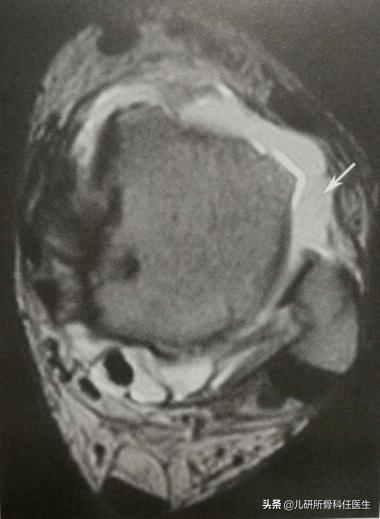

这种情况下,宝爸宝妈们往往能想到的就是拍摄踝关节X线片,但这往往只能排除是否有踝关节骨折。如果想近一步确定韧带损伤的情况,并知晓关节囊及关节软骨损伤的情况,踝关节的核磁共振更有必要。